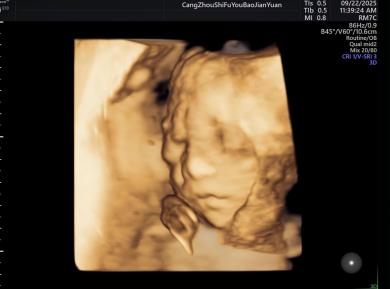

给宝宝的“立体影像”,让产检更安心

科室采用三维/四维超声技术开展胎儿检查,能清晰呈现胎儿面部及身体关键结构的影像,让准父母直观感受宝宝的发育状态。检查中,医生会借助技术对唇腭裂、小下颌等结构异常进行细致观察,同时基于三维容积数据,从多个平面评估胎儿心脏、大脑、脊柱等重要部位,为孕期健康管理提供专业参考。

正常胎儿面部三维照片